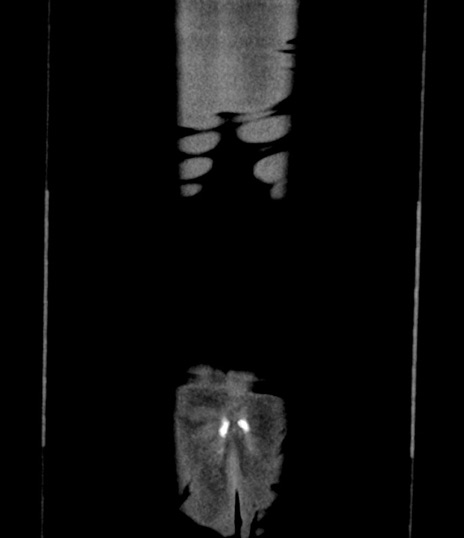

横断像